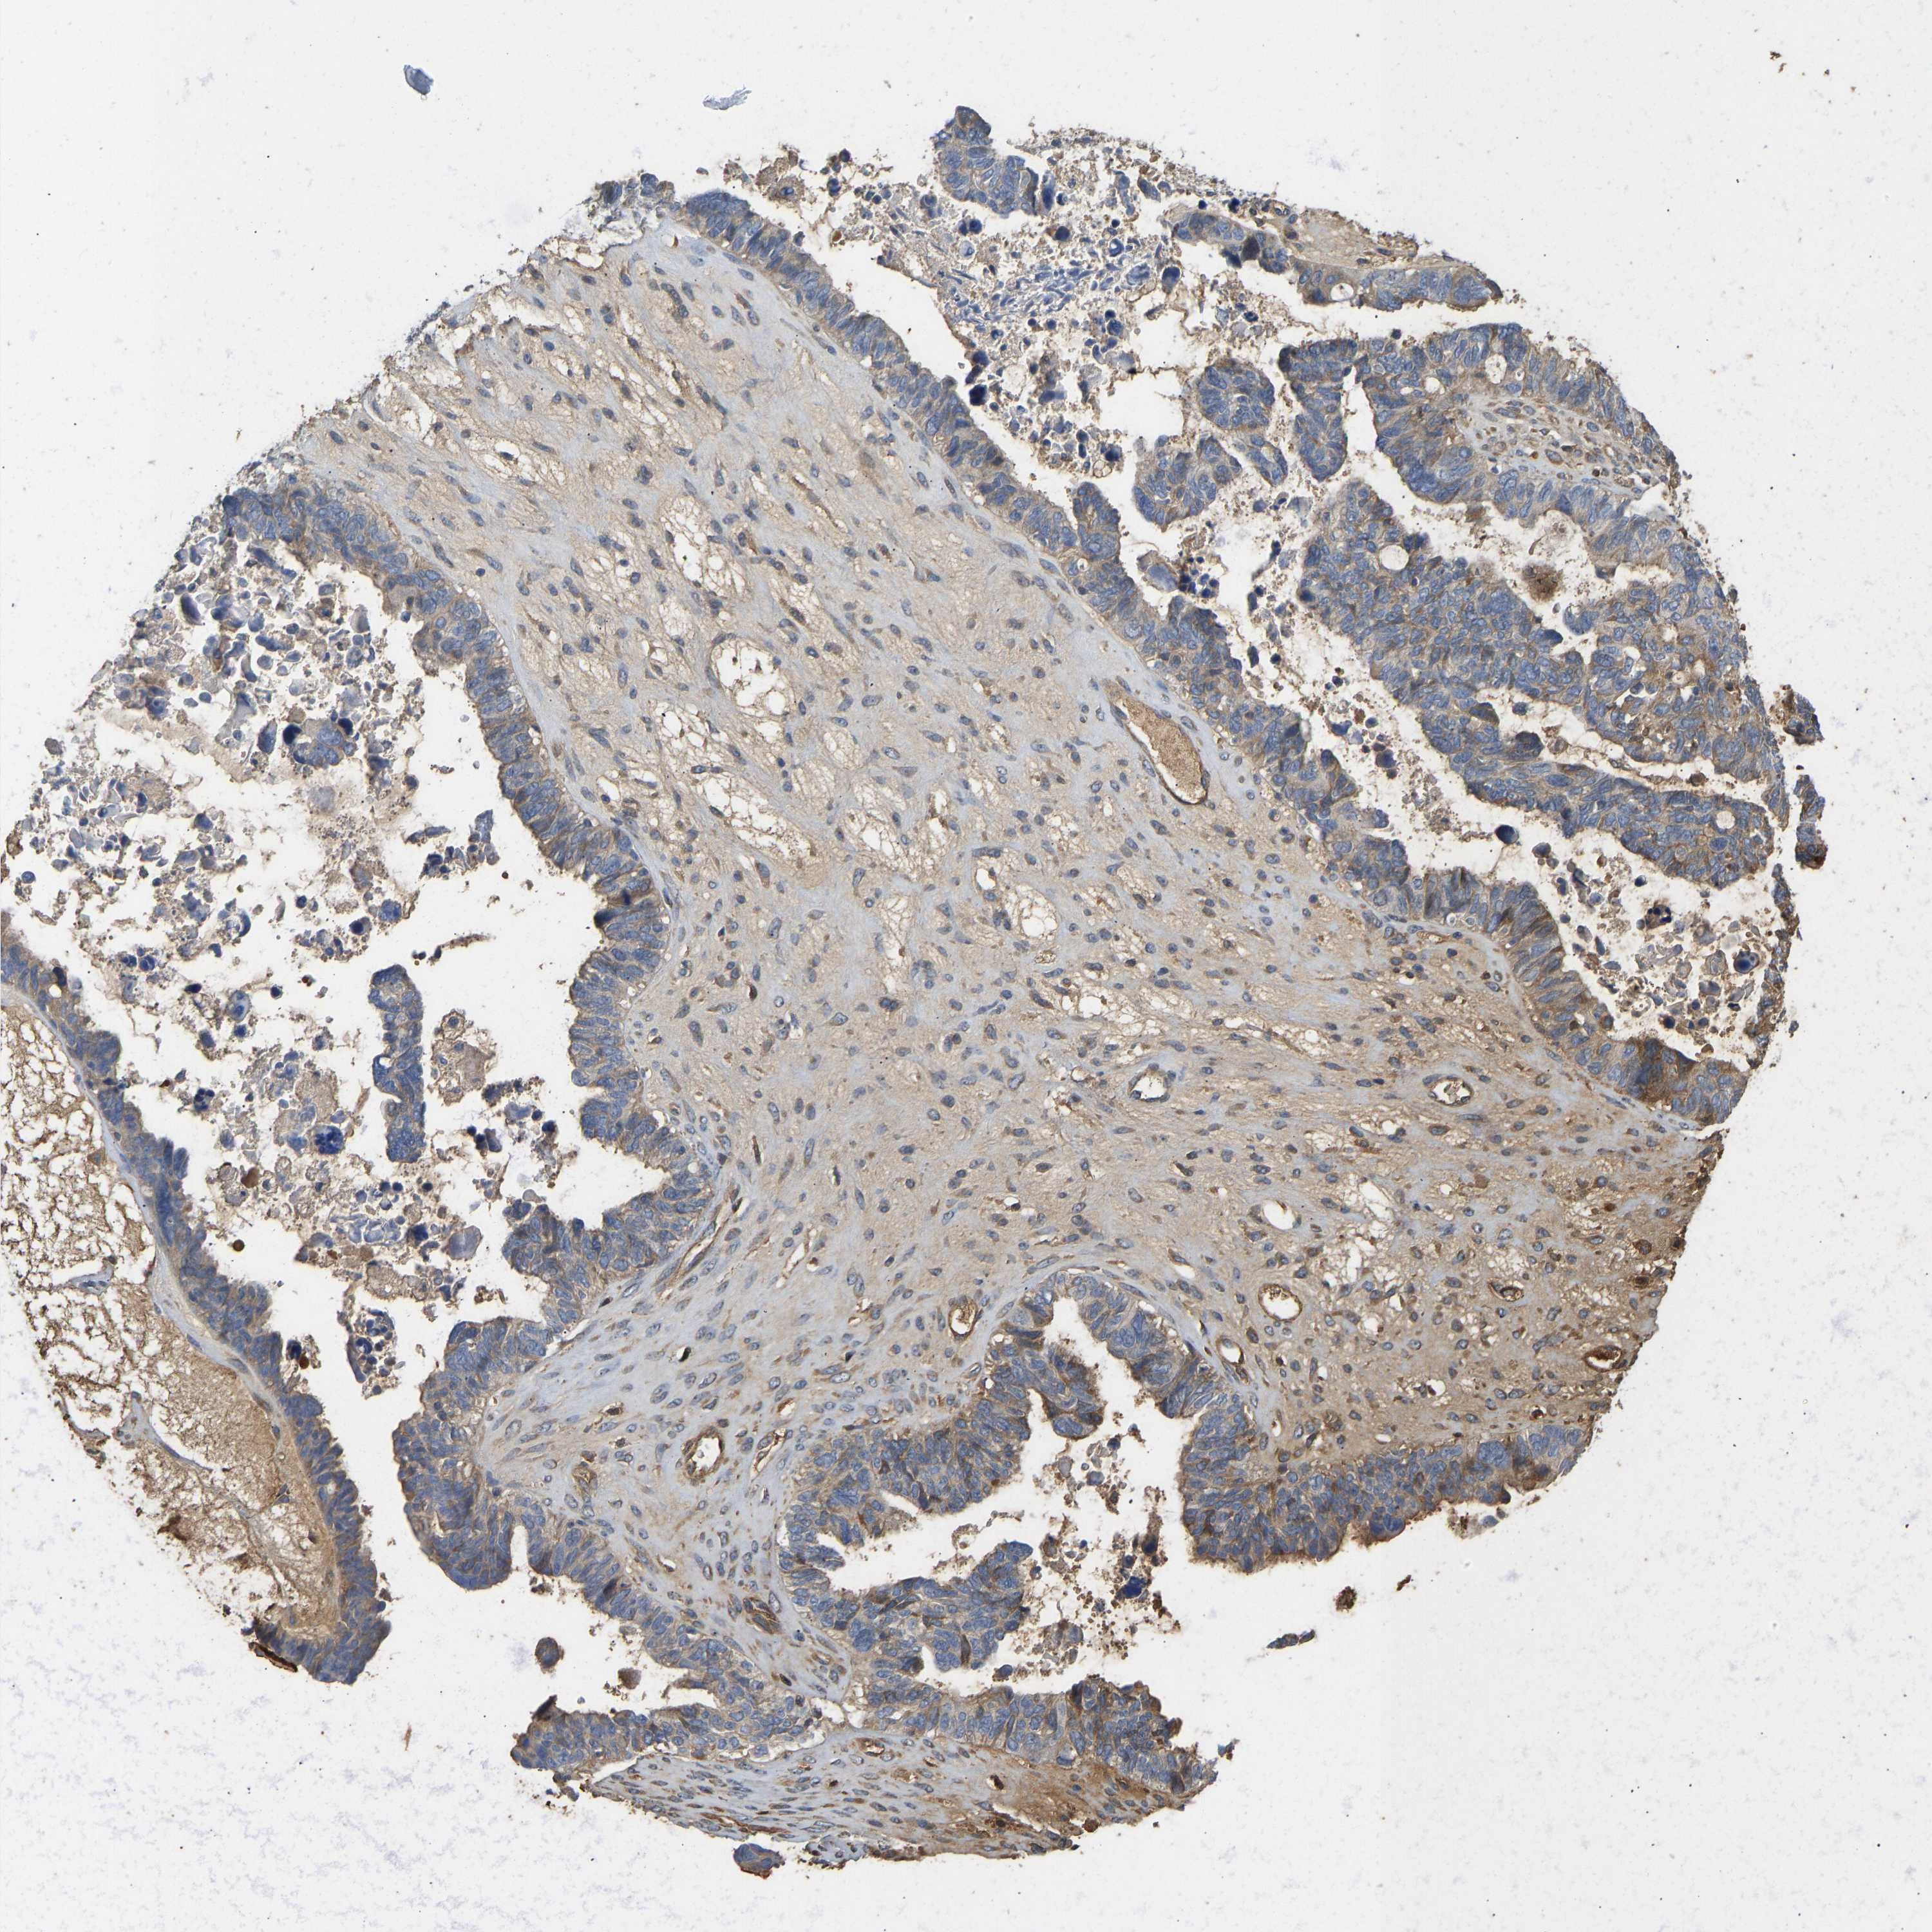

OVARIAN CANCER - Protein expressioni

A mouse-over function shows sample information and annotation data. Click on an image to view it in a full screen mode. Samples can be filtered based on level of antibody staining by selecting one or several of the following categories: high, medium, low and not detected. The assay and annotation is described here.

Note that samples used for immunohistochemistry by the Human Protein Atlas do not correspond to samples in the TCGA dataset.

Antibody stainingi

Antibody staining in the annotated cell types in the current human tissue is reported as not detected, low, medium, or high, based on conventional immunohistochemistry profiling in selected tissues. This score is based on the combination of the staining intensity and fraction of stained cells.

Each image is clickable and will lead to virtual microscopy that enables deeper exploration of all samples and also displays staining intensity scores, fraction scores and subcellular localization as well as patient and tissue information for each sample.

Antibody HPA001146

Staining

High

Medium

Low

Not detected

Intensity

Strong

Moderate

Weak

Negative

Quantity

>75%

75%-25%

<25%

None

Location

Nuclear

Cytoplasmic/membranous

Cytoplasmic/membranous,nuclear

Cystadenocarcinoma, serous, NOS

Carcinoma, endometroid

Cystadenocarcinoma, mucinous, NOS

Carcinoma, NOS